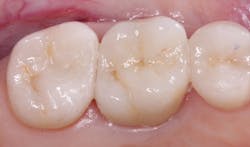

What are the characteristics of a well-accomplished post (figure 3)?

A 1.5 mm to 2.00 mm ferrule around the crown preparation on the marginal area is a highly significant feature. Although there are times when this is impossible due to the short length of the prep and the necessity to avoid harm to the epithelial attachment, the success of the post, core, and crown are compromised if a ferrule is not present. Surgical crown lengthening is an alternative in some clinical situations if it will not compromise the esthetic acceptability of the patient’s smile.

If more than one-half of the tooth’s coronal portion is missing, increasing the antirotational and strength characteristics of the coronal buildup is mandatory by placing retentive metal pins. Pure titanium pins (Filhol Filpin) are ideal because they do not crack the tooth structure, which is usually the case with more rigid stainless steel or titanium alloy pins (figure 4).The submerged post length should be at least one-half of the bony supported length of the tooth. This recommendation is contrary to some suggestions to make the posts extend down three-quarters of the root length. The one-half recommendation, when properly done, is as retentive as placing the post deeper, and it prevents root perforations.

Building up the tooth to simulate a normal tooth prep is accomplished mostly with resin. However, composite and the newer glass ionomers (3M Ketac Universal, GC Equia Forte, and others) can be used in areas not needing high strength. Amalgam is seldom used as a buildup at this time.